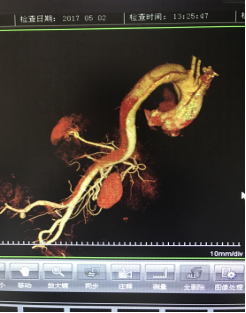

5月2號劉大伯照常早起干活,突然胸部劇烈疼痛,難以忍受,全身大汗,同時伴有右上肢發(fā)涼,他心想這次心絞痛比之前嚴(yán)重的多啊,趕緊叫上孩子到吉林國文醫(yī)院心血管內(nèi)科住院,患者長期高血壓病史,血壓一直控制不理想,大夫給他做了檢查,測左上肢血壓:82/45mmHg,右上肢血壓測不出,心率52次/分,右側(cè)肱動脈、尺動脈、橈動脈搏動消失,左側(cè)股動脈搏動較右側(cè)弱?!霸懔?,雙側(cè)血壓差別這么大,是不是主動脈夾層了?”,接診大夫趕緊找來李主任,李主任反復(fù)詢問患者病情,表情突然凝重起來,患者胸痛這么明顯,血壓低的厲害,主動脈夾層的可能性很大。二話不說,李主任立即聯(lián)系影像科的醫(yī)生準(zhǔn)備做主動脈CTA,移動患者做檢查的過程大夫們非常小心,嚴(yán)密監(jiān)測患者血壓變化情況。兩個小時后結(jié)果出來了,主動脈夾層從升主動脈一直撕裂到左側(cè)髂總動脈!??!

李主任詳細(xì)的與劉大伯的女兒交代了病情,手術(shù)是挽救生命的唯一辦法,為了劉大伯的一線生機,我們積極聯(lián)系了我省權(quán)威的心血管外科,并做了詳細(xì)的匯報,兩家醫(yī)院對此非常重視,為劉大伯開通了綠色通道,安全的把他總到上級醫(yī)院,當(dāng)天便給他進行血管置換及覆膜支架植術(shù)。他術(shù)后恢復(fù)的很好,后來劉大伯的女兒看望我們,感嘆道:沒想到國文醫(yī)院心內(nèi)科應(yīng)急能力這么高,在那么短的時間內(nèi)診斷明確,才給了我的老父親手術(shù)的機會。